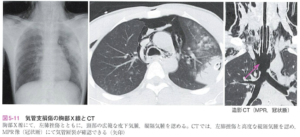

気管分岐部より2.5cm以内の気管断裂像、周囲の縦隔気腫![]() |

気管気管支損傷 |